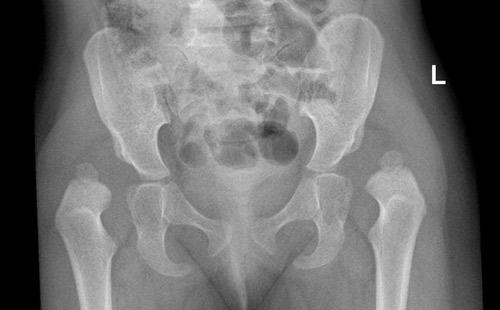

وقال: هناك عدة طرق لاكتشاف المرض وذلك من خلال الكشف السريري لدى الطبيب المختص في جراحه عظام الأطفال والتأكد بأخذ أشعة عادية للحوض تبين من خلالها درجة خلع الورك وما يحتاجه من علاج.